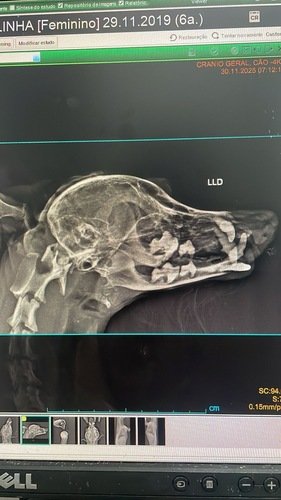

Eu morro de medo de fogos e ontem, por conta do jogo, eu pulei da sacada de casa e estou cheia de machucados - o pior deles é a fratura da mandíbula!!

Estou internada e sendo medicada, porque isso dói muito! Fiz todos os exames e estou me comportando muito bem, mas os tios veterinários falaram que precisarei de cirurgia!